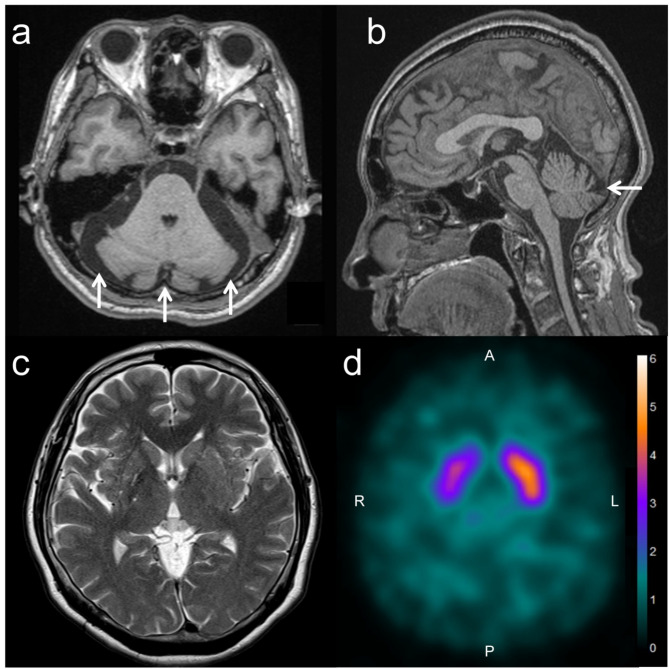

Case presentation: A 62-year-old woman presented with involuntary movements in her right limbs that occurred intermittently for two weeks. Her medical and medication history was unremarkable and she had a paternal grandmother who was diagnosed with Parkinson's disease. Neurological examination revealed right-sided hemichorea without other abnormalities. Head magnetic resonance imaging (MRI) did not reveal acute ischemic or hemorrhagic lesions; instead, it displayed mild cerebellar atrophy. In addition, dopamine transporter-single photon emission computed tomography (DAT-SPECT) detected bilaterally decreased striatal tracer uptake. Although she had no relatives with similar symptoms or SCA, a set of genetic molecular tests for SCA was conducted because she had mild cerebellar atrophy found on MRI. It detected CTA/CTG repeat expansion in the ATXN8OS gene (18/125 repeats; normal range: 15-50). She was diagnosed with SCA8, which was considered the cause for her hemichorea. Oral haloperidol was initiated as symptomatic treatment and it largely resolved her hemichorea.

Conclusions: We should remember that patients with SCA8 can present with hemichorea as the sole clinical manifestation. Moreover, DAT-SPECT may detect their nigrostriatal hypofunction even if they do not have clinically apparent parkinsonism.